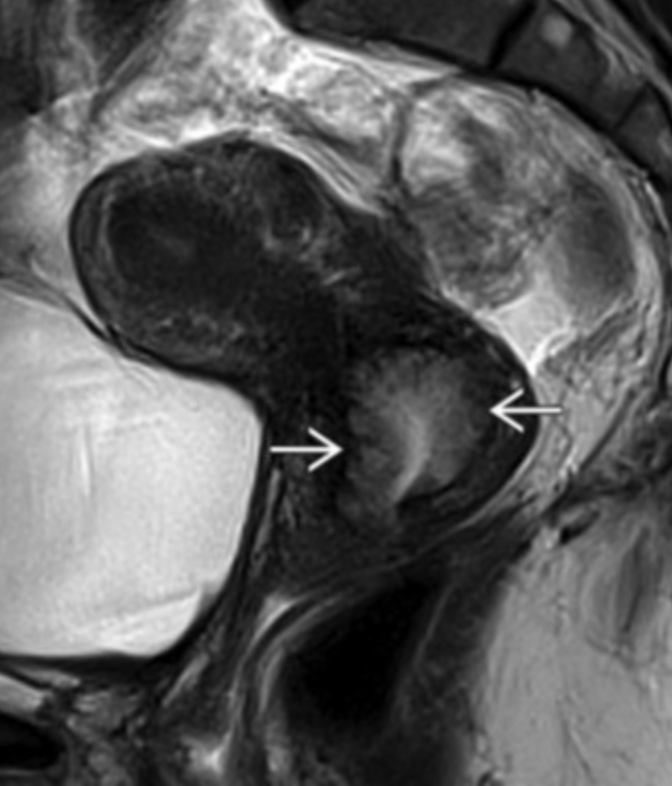

• Specific to MR

• Thick junctional zone with indistinct margins

• T2 bright foci in endometrial & myometrium (sometimes T1 bright too)

• This is how you differentiate it from a fibroid